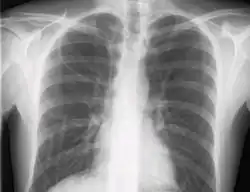

The line is then inserted using the Seldinger technique: a blunt guidewire is passed through the needle, then the needle is removed. A dilating device may be passed over the guidewire to expand the tract. Finally, the central line itself is then passed over the guidewire, and the wire is then removed. All the lumens of the line are aspirated (to ensure that they are all positioned inside the vein) and flushed with either saline or heparin.[1] A chest X-ray may be performed afterwards to confirm that the line is positioned inside the superior vena cava and no pneumothorax was caused inadvertently. On anteroposterior X-rays, a catheter tip between 55 and 29 mm below the level of the carina is regarded as acceptable placement.[10] Electromagnetic tracking can be used to verify tip placement and provide guidance during insertion, obviating the need for the X-ray afterwards.

If a pneumothorax is suspected, an upright chest x-ray should be obtained. An upright chest x-ray is preferred because free air will migrate to the apex of the lung, where it is easily visualized. Of course, this is not always possible, particularly in critically ill patients in the intensive care unit. Radiographs obtained in the supine position fail to detect 25–50% of pneumothoraces.[12] Instead, bedside ultrasound is a superior method of detection in those too ill to obtain upright imaging.[3]

During subclavian vein central line placement, the catheter can be accidentally pushed into the internal jugular vein on the same side instead of the superior vena cava. A chest x-ray is performed after insertion to rule out this possibility.[32] The tip of the catheter can also be misdirected into the contralateral (opposite side) subclavian vein in the neck, rather than into the superior vena cava.